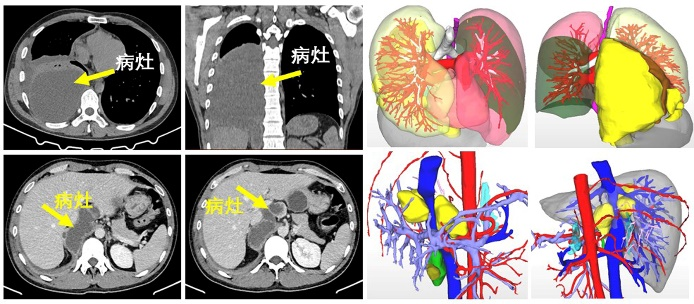

这是一名年轻男性患者,因「右上腹及肩背部疼痛 5 天」来到肝胆胰外科就诊。经胸部增强 CT 检查提示右胸腔后侧、下纵膈气管旁囊性占位性病变,右肺下叶压缩性肺不张。腹部增强 CT 提示肝包虫病,腹膜后多发囊性占位病变,考虑为包虫病。

肝胆胰外科杨闯主任认为患者为藏区群众,有疫区接触史,结合影像学资料,肝棘球蚴病、腹腔棘球蚴病、胸腔棘球蚴病明确,需要手术治疗。因病灶涉及多系统器官,手术较复杂,需要多学科协作完成,在医院医务部罗亦刚主任的主持下,杨闯副院长邀请郭中恒院长、麻醉科曾浩主任等科室负责人开展 MDT(多学科会诊)讨论。

通过讨论一致认为,从多维度考量,胸、腹部病灶同期手术切除的方案是可行的,取得患者家属同意后,决定为患者实施胸腹腔病损切除、右肺部分切除、肝部分切除等手术。

经充分术前准备,赵科医生担任主麻,曾浩主任为麻醉指导,郭中恒主任医师主刀为患者实施右侧胸部病损切除、部分肺切除术,接着由杨闯主任医师为患者实施肝部分切除联合腹膜后包虫切除术,历经近 9 小时奋战,手术顺利完成。